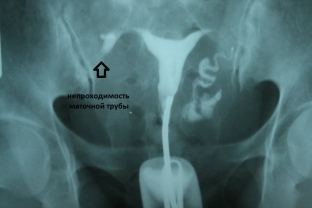

- гістеросальпінгографія – рентгенконтрастне дослідження, яке найкраще візуалізує спайкові процеси в органах малого тазу;